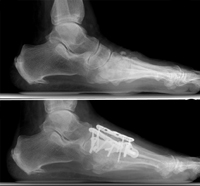

(Top) This x-ray shows RA of the midfoot that has collapsed the arch.(Bottom) The surgical reconstruction involved a fusion of the middle of the foot with plates and screws.